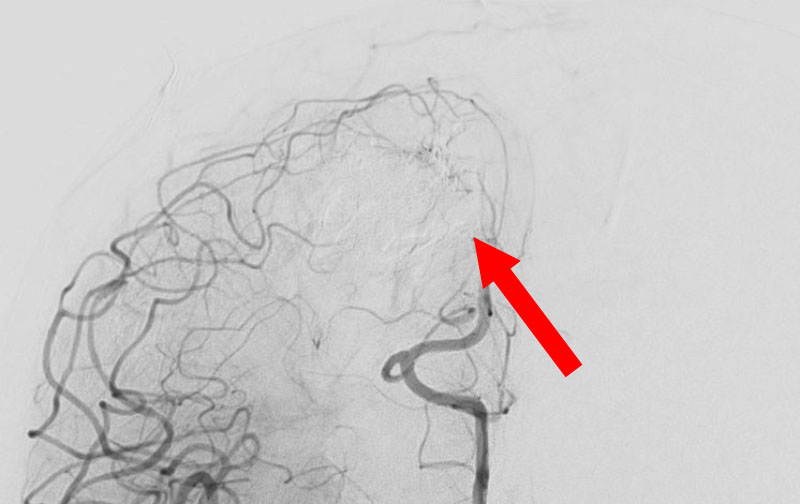

1585

'25年10月6日

脳動静脈奇形

50代

大阪府の病院

後

治療